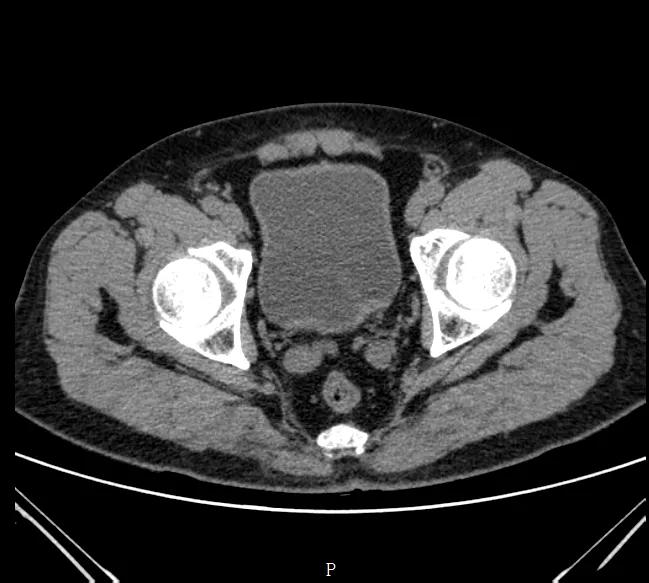

尽管做了这些,但还是不够明确,于是又做了一个泌尿系统CT,

泌尿系CT结果是:

此次检查仅提示膀胱局部增厚、膀胱内凝血块。那等于说也是没有检查出什么问题,和第二次检查结果差不多。